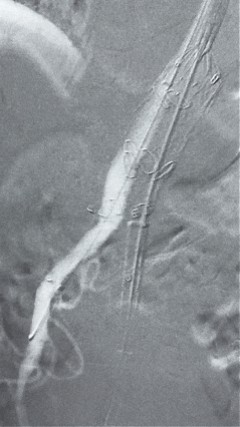

8. 从右侧股动脉入路送入腹主支架AB-24-12-110-S,近端重叠胸腹主动脉支架远端,调整好支架位置后释放。

9. 经左股动脉送入导丝导管,超选进腹主动脉支架短腿内,后沿导丝送入髂支,同理,右侧沿导丝送入髂支并释放,使用九州ku酷游顺应性球囊后扩各支架连接处及支架近远端,最后通过预留导管向瘤腔注入人纤维蛋白粘合剂数支,造影显示分支通畅。

G-Branch在本例手术中展现出对扭曲解剖结构的出色适应性,针对该患者严重扭曲的瘤颈,支架系统的优异柔顺性使其能够顺利通过复杂路径,完成内脏分支血管的重建。

其独特的双内嵌、双外翻混合多分支设计兼顾了操作效率与结构可靠性,预置导丝系统简化了肠系膜上动脉(SMA)和腹腔干动脉(CA)的超选流程,显著提高手术效率。